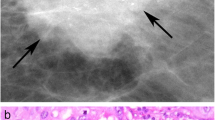

Benign lesion showing psamomatous calcifications (a haematoxylin eosin stain; b TEM micrograph) composed of calcium oxalate (c EDX spectrum). Malignant lesion showing amorphous calcifications (d and g haematoxylin eosin stain; E and H TEM micrographs) composed of hydroxyapatite (f EDX spectrum) or hydroxyapatite Mg substituted (i EDX spectrum). a, d, g scale bar represent 50 μm. b, h scale bar represent 0,2 μm (e) scale bar represent 1 μm